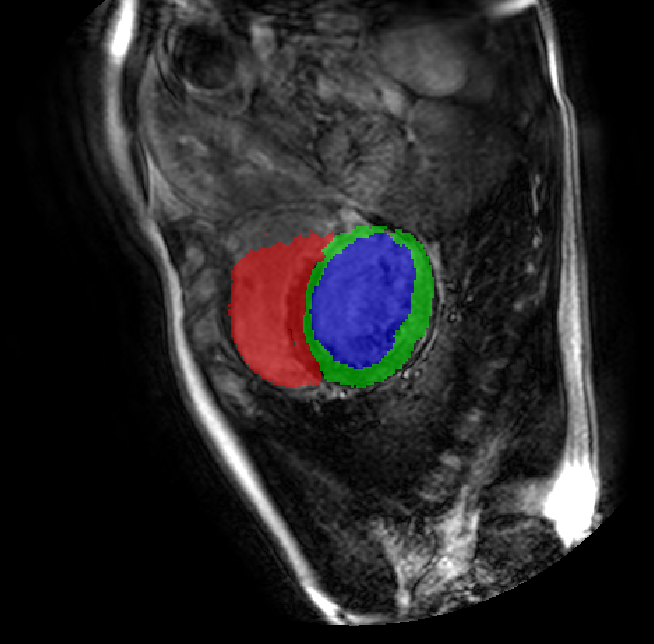

Table 2 presents an ablation study and compares SparseMamba-PCL with nine SOTA scribble-supervised methods across the three datasets. Out method achieves the highest Dice score across all the datasets, and the lowest (CHAOS) and second lowest (ACDC and MSCMRSeg) HD95 values, confirming its effectiveness in segmentation accuracy and boundary refinement. Baseline+SPOBE and Baseline+PCL improve upon the Baseline (SparseMamba), demonstrating the benefits of boundary-aware supervision and SAM-guided learning. Fig. 4 (l) compares the segmentation performance of SparseMamba-PCL with other scribble-supervised methods, showing smoother edges that precisely delineate object boundaries, unlike the jagged or blurred edges in other methods. The examples also demonstrate the consistent segmentation quality achieved by SparseMamba-PCL across ACDC, CHAOS, and MSCMRSeg, highlighting its adaptability across multiple medical domains. This adaptability and precise segmentation is crucial for accurate volumetric analysis and clinical decision-making, where even subtle boundary inaccuracies can lead to diagnostic errors. In summary, the SparseMamba-PCL architecture provides a consistent and robust improvement in segmentation metrics across diverse medical image datasets.

Refer to caption Refer to caption Refer to caption Refer to caption Refer to caption Refer to caption Refer to caption Refer to caption Refer to caption Refer to caption Refer to caption Refer to caption

(a) (b) (c) (d) (e) (f) (g) (h) (i) (j) (k) (l)

Figure 4: Qualitative comparison of weakly-supervised segmentation methods on ACDC, CHAOS, and MSCMRSeg datasets. (a) Input image, (b) ground truth, and segmentation results from (c) USTM [16], (d) Scribble2D5 [5], (e) CycleMix [26], (f) ShapePU [27], (g) S²ME [21], (h) ScribbleVC [12], (i) TDNet [30], (j) PacingPseudo [25], (k) Scribbleformer [13], and (l) SparseMamba-PCL are given.